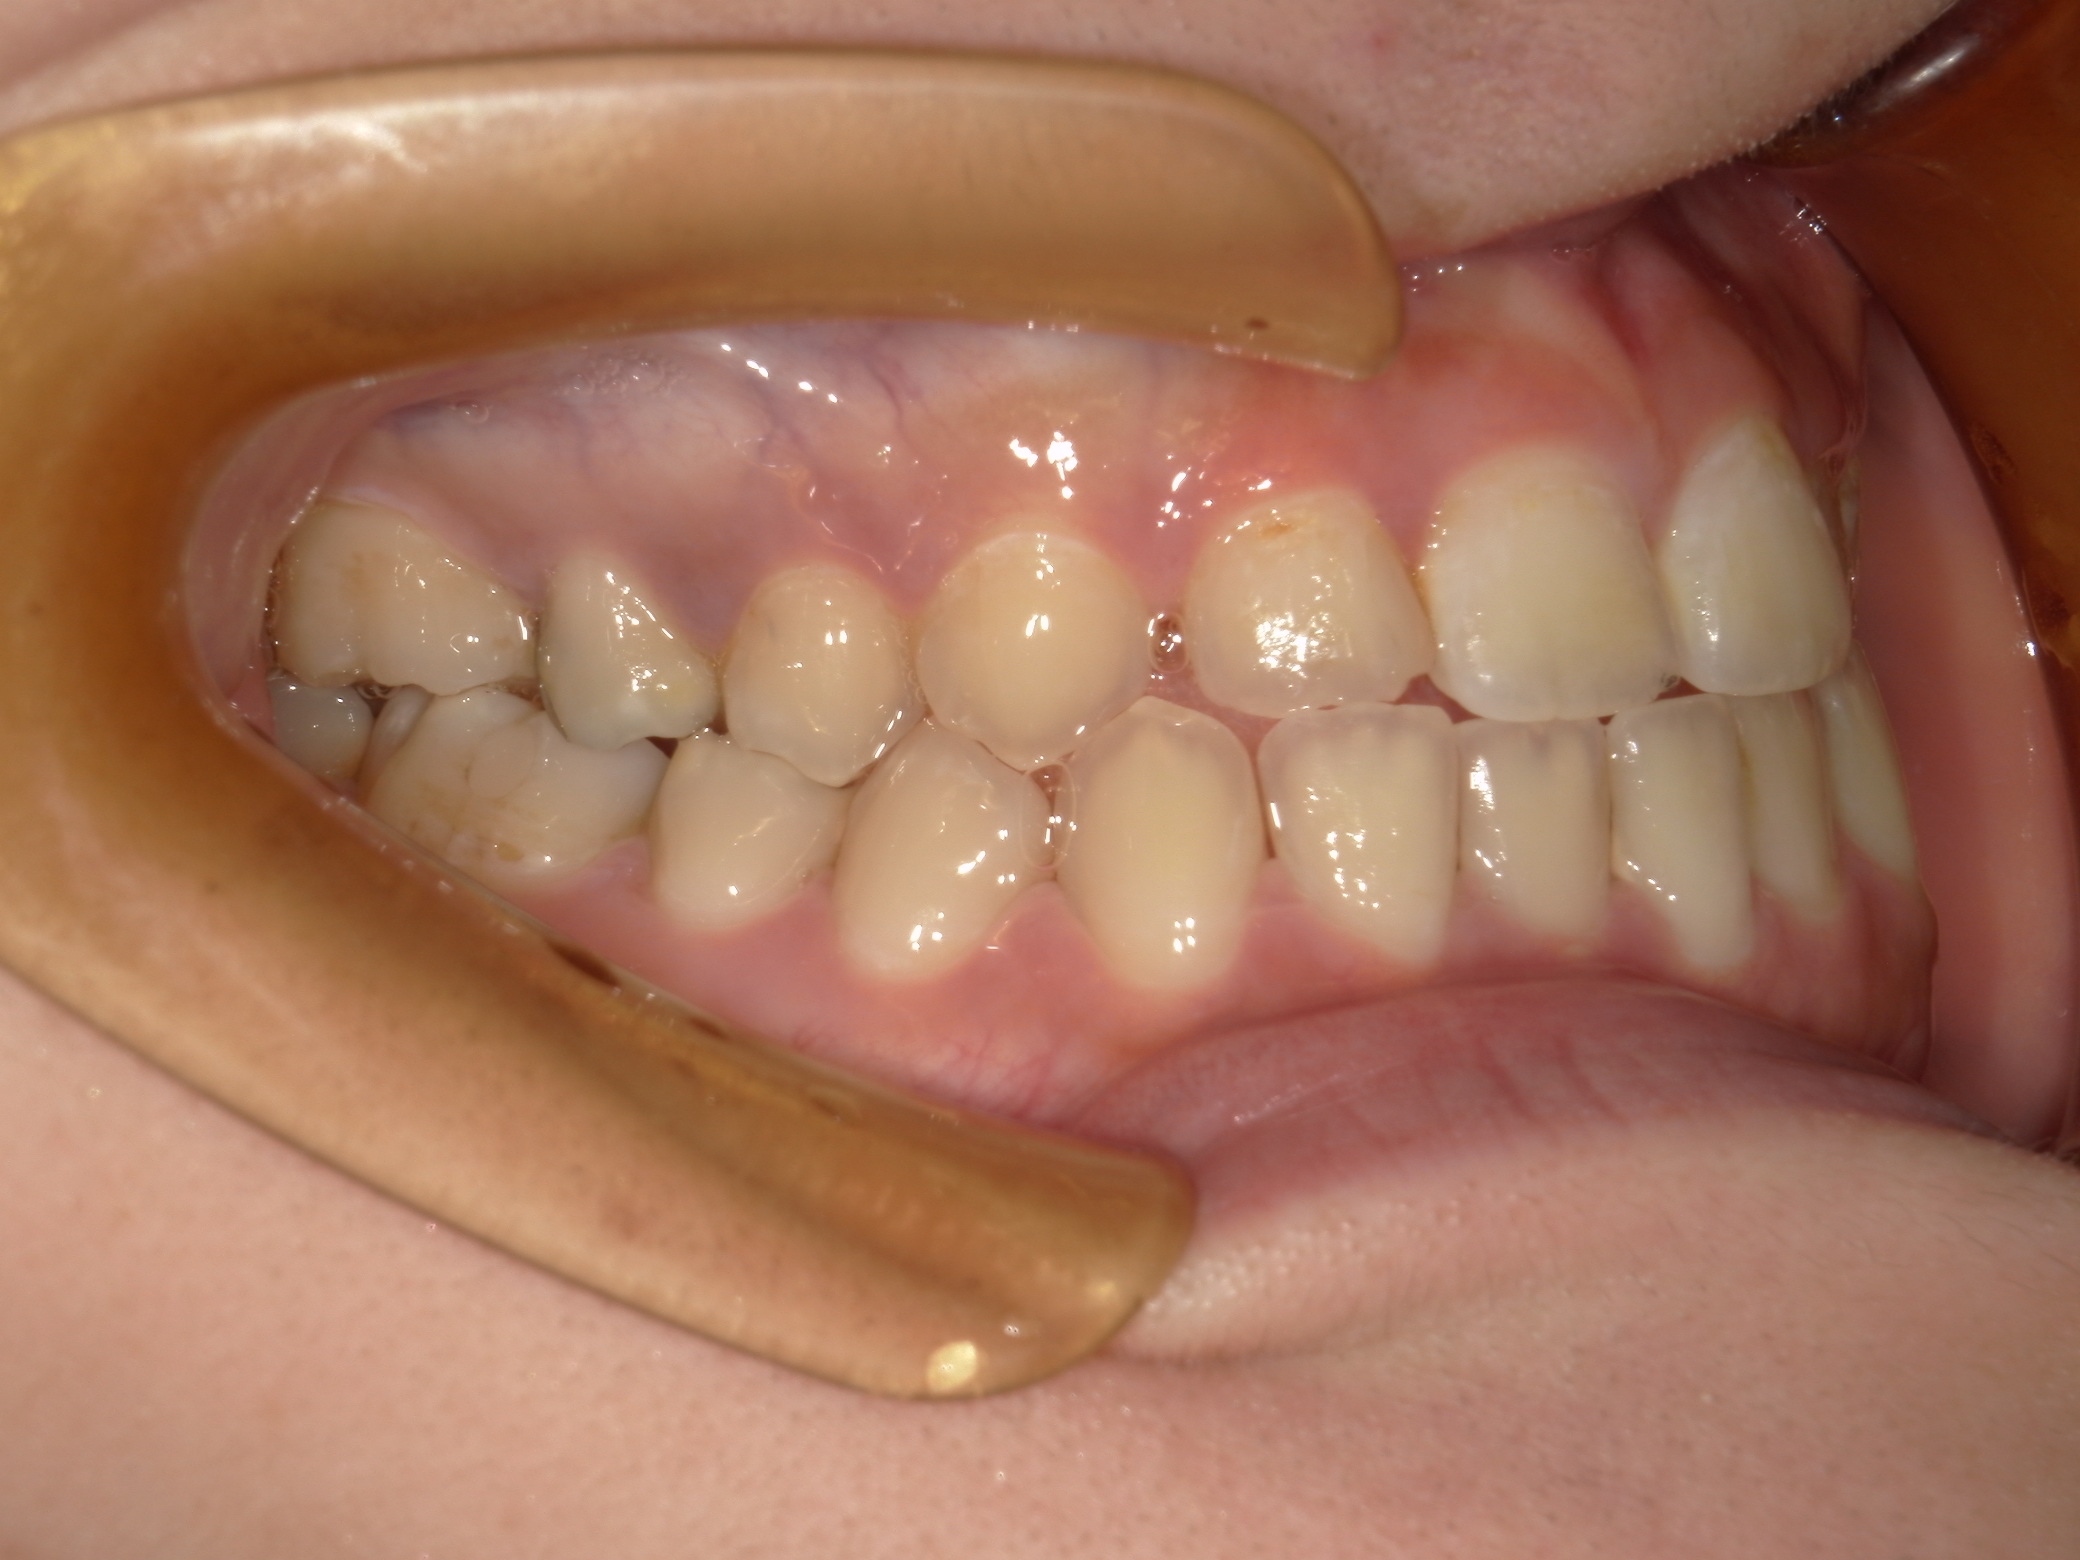

口内右

治療前

治療後